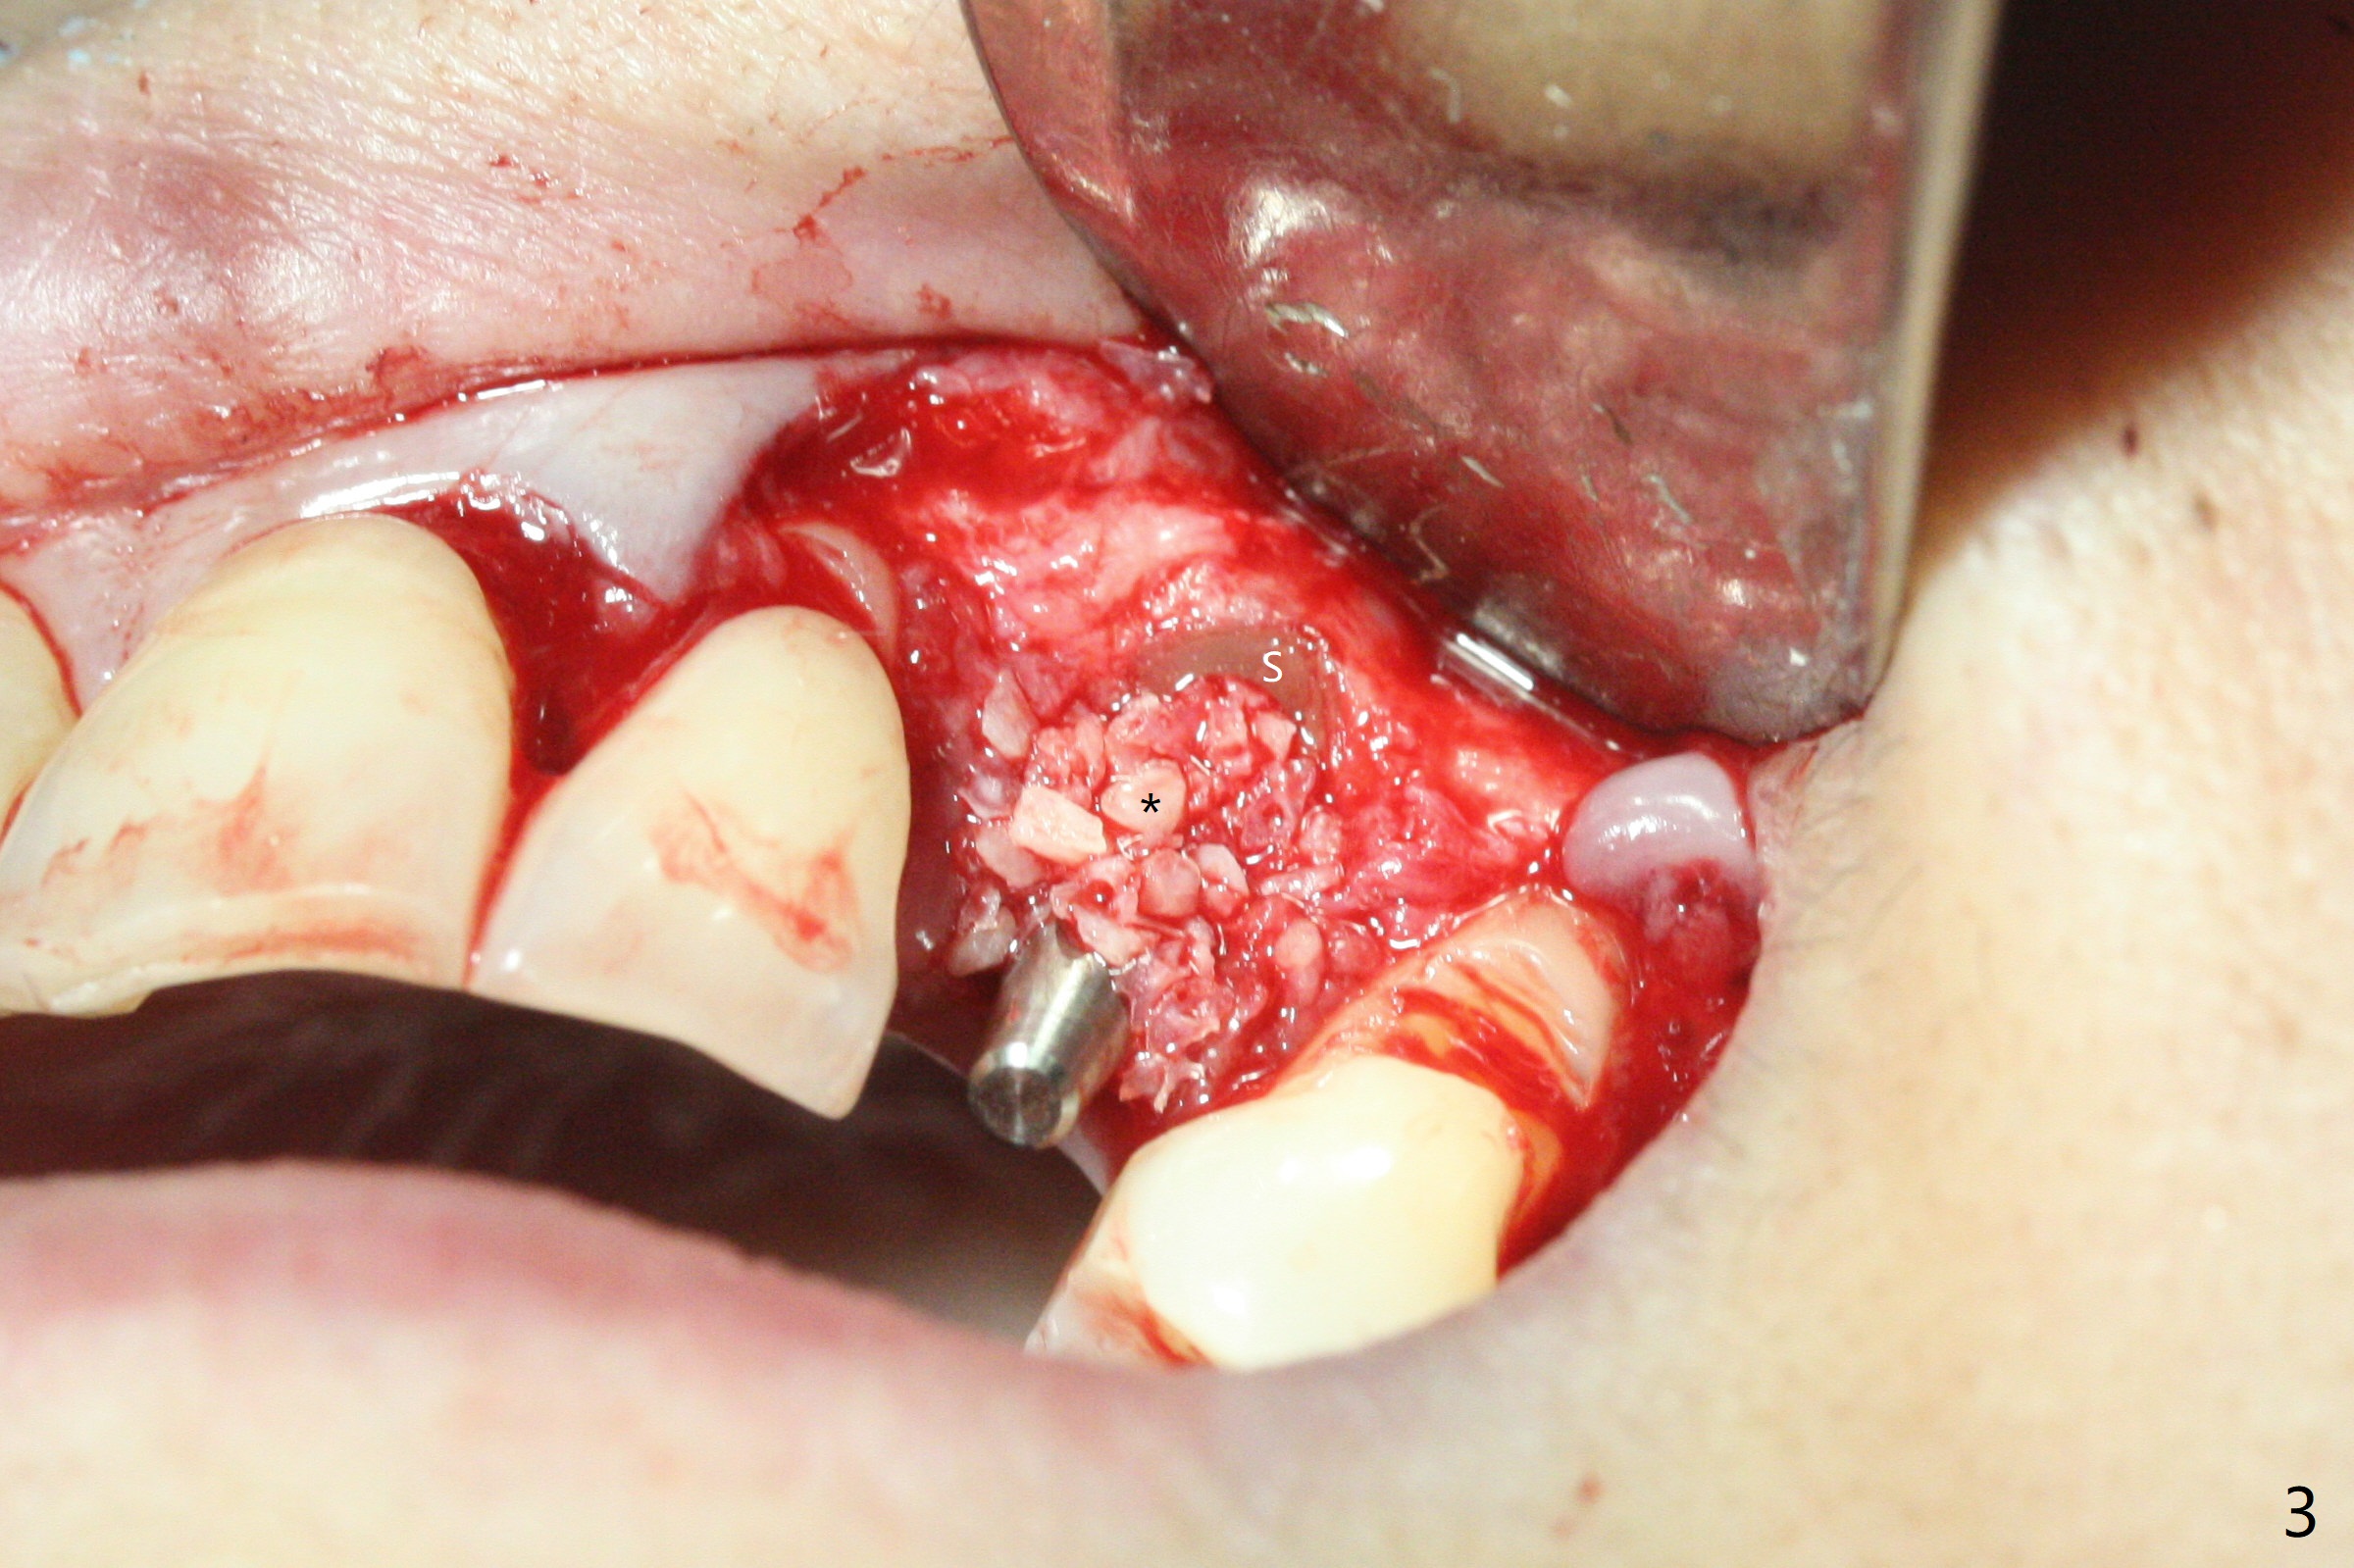

At surgery, the mesiodistal space for #11 is found to be narrow, 5 mm. To prevent buccal plate collapse, socket shield is planned. Due to limited space, incision is attempted so that the lower end of the shield (Fig.1 S) can be trimmed slightly subcrestal. It is also good for visibility for osteotomy (1.2 mm drill for 12 mm). A 2.5x14(2) mm 1-piece implant is placed with <35 Ncm (Fig.2,3 (*: allograft)). An immediate provisional is fabricated to the patient's satisfaction. There is no bone loss 3.5 months postop (Fig.4) or 4 months postop (Fig.5 *, corresponding to S in Fig.3). The recessive papillae are expected to reform to certain degree due to limited damage to the crestal bone.